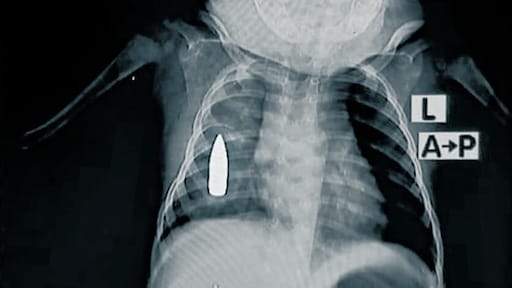

Precies die oorzaken zijn dankzij de röntgenfoto's nu duidelijk zichtbaar. Zo zie je in de foto boven dit artikel duidelijk een kogel zitten in de borstkas van een 18 maanden oude dreumes.

Dit jaar alleen al werden in het ziekenhuis 314 kinderen met kogelwonden behandeld, onder wie het kindje van de foto boven dit artikel.